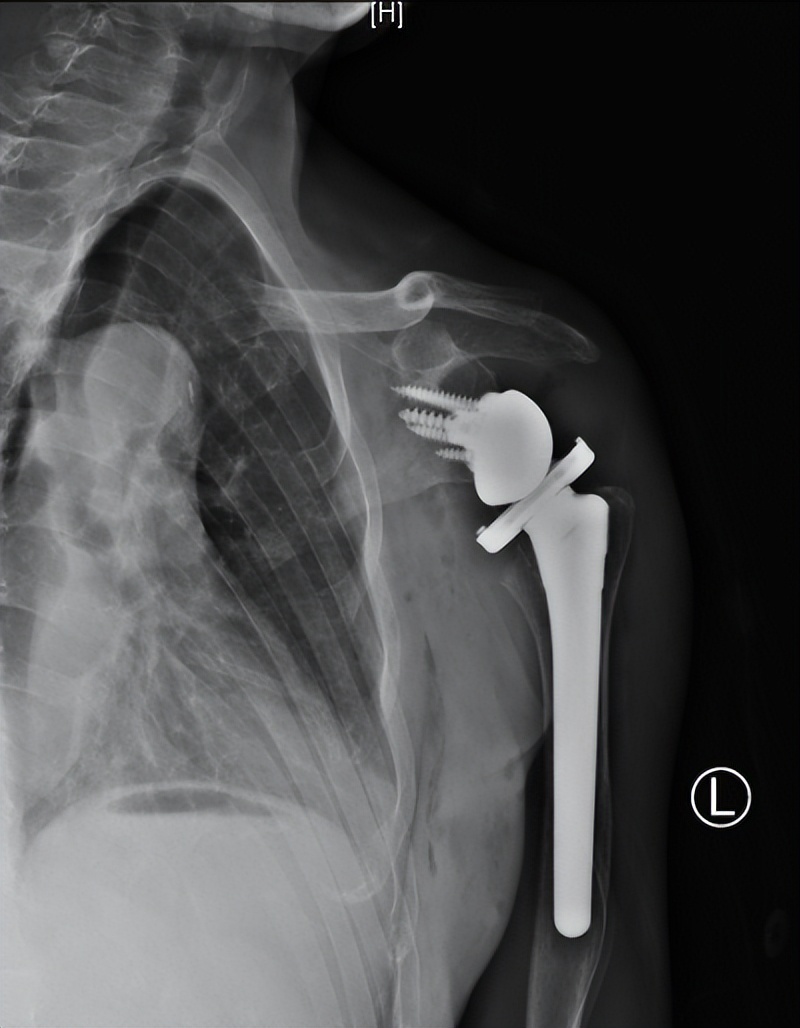

术后X线

在麻醉手术科医护人员的配合下,创伤中心成功实施了“反置式人工全肩关节置换术”,采用人工假体替代受损的肱骨头和关节盂。术后陈大爷恢复顺利,在科室康复医师的帮助下进行康复锻炼,功能获得明显改善。

反式人工全肩关节置换术是指肩关节假体的球形关节面置于肩胛骨关节盂侧,而盂杯放置于肱骨近端的半限制性人工全肩关节。反肩置换术是肩关节复杂毁损性病变的拯救术式,是利用三角肌来替代肩袖的动能,但由于对适应证限制,手术难度等原因,在国内开展较少。反肩置换主要适用于难以复位固定的老年肱骨近端骨折、陈旧性肱骨近端骨折不愈合或合并骨缺损、骨折内固定失败翻修、难以修复的巨大肩袖撕裂等。作为山东省医师协会骨科分会主委单位、山东省医师协会肩肘外科专业委员会主委单位,创伤中心多年致力于肩肘复杂创伤的研究,该疑难手术的顺利实施,体现了我院处理复杂肩肘创伤病例的领先能力。